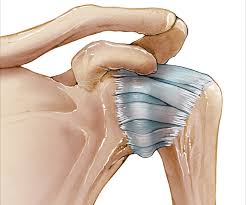

오십견은 유착성 관절낭염이나 동결견(frozen shoulder)라는 다른 이름으로 명명되어 지는데 임상적으로 볼 때 운동제한을 동반한 어깨 통증과 야간통증이 있을 때 의심하게 되는 질병으로 운동범위 검사와 어깨 MRI를 통해서 진단한다고 한다.

일반적으로 외상이나 지속적인 고정 후에 발병하지만 회전근개의 질환이나 석회성 건염 같은 질환, 또는 중풍, 심근경색, 당뇨 등에 의해 속발성으로 나타나기도 한다고 한다.

통증은 외전, 외회전, 신전시킬 때 악화되며 삼각근 부착부와 위팔의 바깥쪽으로 통증이 전해지기도 한다고 한다.